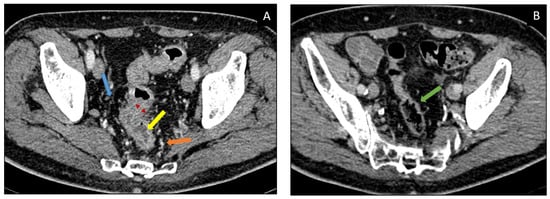

11.3. Diagnosis and Imaging

| Imaging Modality | Findings |

| CT MRI |

| PET-CT (18F-FDG) |